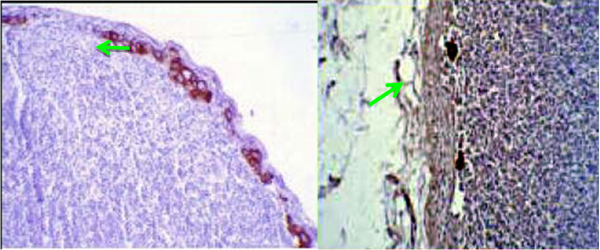

החומר הרדיואקטיבי מוזרק כארבע שעות עד 24 שעות לפני ניתוח. לאחר הזרקתו בעזרת מיפוי אפשר להדגים את מקום הבלוטה ולסמן את מיקומה על העור. ניתן להדגים גם בלוטות הקולטות חומר בשרשרת האינטרנל ממרי. בחדר ניתוח ניתן לאתר את הבלוטה בעזרת מונה גייגר על העור ובשדה הניתוח (תמונה 52.12).

שיטת בלוטת הזקיף מאפשרת לפתולוג לעבד את הבלוטה בצורה טובה יותר (יותר חתכים) מה שגרם לזיהוי של יותר בלווטת כנגועות. בעיקר עלה שיעור הבלוטות הנגועות המאובחנות כבעלות מיקרו-גרורה (קבוצת תאים שגודלם בין 0.2-2 מ"מ) או על ידי תאים בודדים (קבוצות הקטנות מ- 0.2 מ"מ). הכנסת שיטות אימונוהיסטכימיות לזיהוי תאי אפיתל בבלוטה (צביעות ציטוקרטין – CK) העלה עוד יותר את שיעור הבלוטות הנגועות המאובחנות (תמונה 53.12 ו- 54.12). הסוגיה של המשמעות של תאים בודדים בצביעת ציטוקרטין אינה ברורה, כי הוכח שתאי אפיתל מתים יכולים להמצא גם בבלוטות תקינות, ולכן בשלב זה בלוטות עם גרורות הנראות רק ב-CK - ההתיחסות אליהם היא כאילו אין גרורות. בחולות עם מיקרו–גרורות נמצא שעם המיקרו-גרורה היא בבלוטה אחת, הסיכוי שנמצא עוד בלוטות נגועות הוא כ-15% , אולם ברובם תהייה זו בלוטה עם מיקרו–גרורה. לכן, מוסכם כיום שבחולות עם מיקרו-גרורות אין צורך להמשיך לכריתת מכלול הבלוטות בבית השחי.